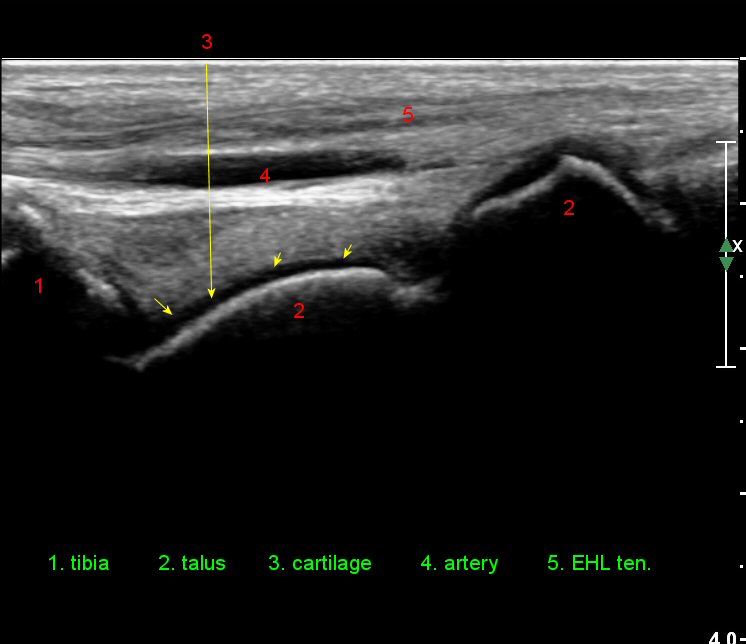

¹ß¸ñ°üÀý ¾ÕÂÊ Á¾´Ü¸é°Ë»ç¿¡¼­ ƯÀÌ ¼Ò°ßÀ» º¸ÀÌÁö ¾ÊÀ¸³ª(»çÁø 1)

ŽÃËÀÚ¸¦ ÀÎÁ¢ÇÑ ºÎÀ§·Î À̵¿ÇÏ´Ï ¼Ò·®ÀÇ °üÀý³» ¼ö¾×Àú·ù°¡ °üÂûµÈ´Ù(»çÁö 2).

Àü¹æ °æ°ñºñ°ñÀδë Á¾´Ü¸é°Ë»ç¿¡¼­ ƯÀÌ ¼Ò°ßÀ» º¸ÀÌÁö ¾Ê´Â´Ù(»çÁø 3).

Àü°ÅºñÀδë Á¾´Ü¸é°Ë»ç¿¡¼­ ¾È´ë ºñ°ñ ºÎÂøºÎÀÇ Àú¿¡ÄÚ ºÎÁ¾°ú ºÎºÐÆÄ¿­ÀÌ °üÂûµÈ´Ù(»çÁø 4).